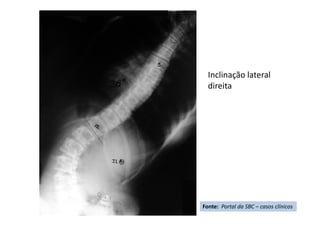

Inclinação lateral

direita

Fonte: Portal da SBC – casos clínicos

Apresentação de Casos Clínicos

• Escoliose Idiopática do Adolescente

• Resumo do caso: Escoliose idiopática do adolescente tratada

cirurgicamente com artrodese da coluna T4L1 com parafusos

pediculares.

• Paciente (dados): feminino, 13+2 anos, Risser 3, menarca há

9 meses.

• História: Deformidade da coluna percebida pela mãe há 3

meses. Nega tratamento prévio. Nega demais doenças ou uso

de medicações.

• Diagnóstico(s): Escoliose idiopática do adolescente, Lenke

1B-. Tratamento(s): Artrodese da coluna por via posterior T4-

L1 com parafusos pediculares.

• Seguimento ("Follow up"): Seguimento de 2

anos. Literatura:

• Resultado Final: Artrodese seletiva torácica T4-L1, obtida

compensação do tronco e nivelação dos ombros.